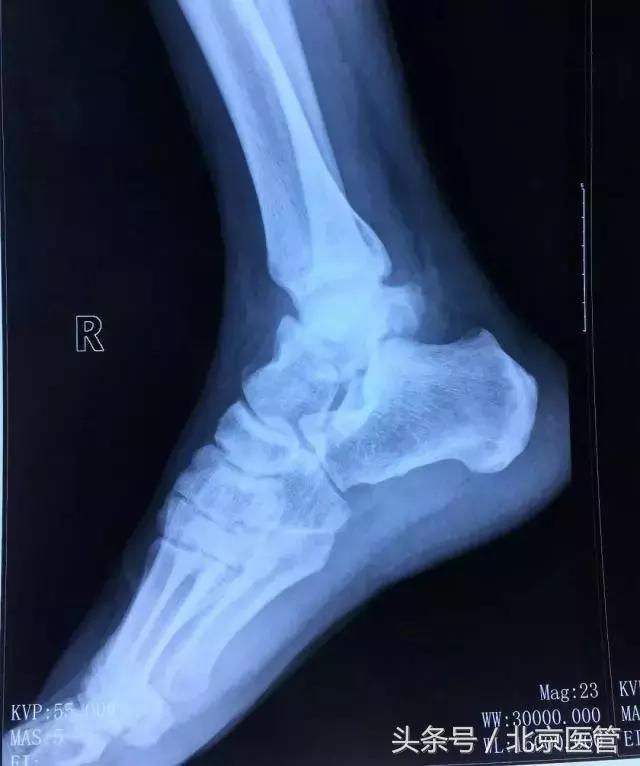

本例患者为48岁,男性,从高处坠落导致距骨体粉碎性骨折(右,Sneppen II型)。应用新技术后在很短的时间内完成微创手术,骨折固定精准稳定。

术前影像